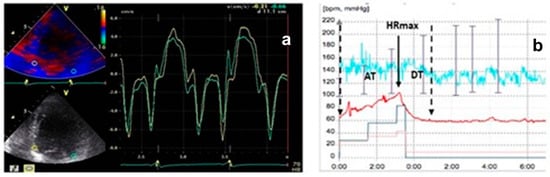

In super-responders, a substantial LV reverse remodeling was observed (LVEDV 193.7 ± 81 vs. 243.2 ± 82 mL at baseline; p < 0.0028), along with reduced LV filling pressures (E/E′ 13.2 ± 4.6 vs. 11.4 ± 4.5; p = 0.0295). These changes correlated with improvements in the resynchronization parameters we studied. The E″T decreased from 90 ± 20 ms to 25 ± 10 ms and was associated with a shorter deceleration time during ET compared to NR (109 ± 68 ms vs. 330 ± 30 ms; p < 0.0001) (Figure 4).

Figure 4.

(a) Super-responders’ TDI pattern; green line = lateral velocity curve; yellow line = septal velocity curve. (b) HRRI diagram in super-responders; red line = heart rate.

An important consideration in our study is the interindividual variability in exercise performance, which may have influenced the HRRI measurements. Despite utilizing the Bruce protocol, patient responses to exercise can differ markedly due to variations in baseline physical conditioning, the presence of comorbidities, and other uncontrolled factors. This variability introduces a potential limitation regarding the reproducibility and consistency of HRRI values. The CRT evaluation during ET encompassed minimum and maximum heart rate, acceleration time (AT), deceleration time (DT), and the AT/DT ratio denoted as the heart rate recovery index (Figure 3).

Figure 3.

Graphic representation of the heart rate recovery index (HRRI = AT/DT). B = begin exercise; S = stop exercise; HR = heart rate; HRmax = maximum heart rate; AT = acceleration time; DT = deceleration time (adapted with permission from Cozlac et al. [6]).